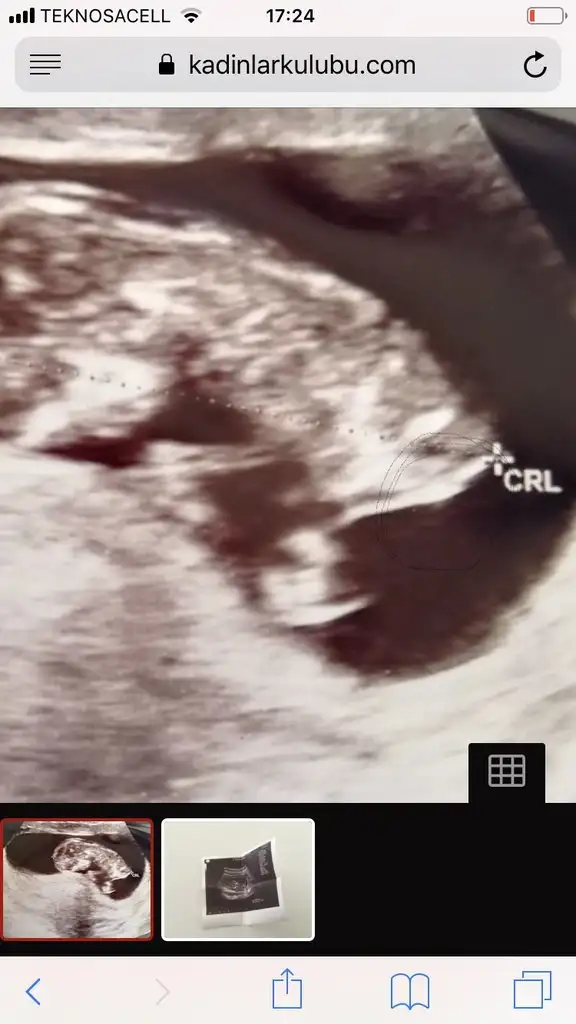

Göbek bağı da var ama, çok kıbırdamış hareketliymiş o an belliSelam kızlar bende ocak 2020 annesiyim. Cinsiyeti yarın öğrencem. Yanlız bi ultrason görüntüm var geçen haftaki ultrasondan, orda bi çıkıntı var ama dr cinsiyeti söylemedi. Sizce bu çıkıntı göbek bağı mı pipi mi?

Hayırlı olsun :) nub teorisinden bahsedildi belki okumussunuzdur. Ben erkege benzettim. Beline gore yukari dogru hafif acili bi çıkıntı var gibi :)Selam kızlar bende ocak 2020 annesiyim. Cinsiyeti yarın öğrencem. Yanlız bi ultrason görüntüm var geçen haftaki ultrasondan, orda bi çıkıntı var ama dr cinsiyeti söylemedi. Sizce bu çıkıntı göbek bağı mı pipi mi?

Selam kızlar bende ocak 2020 annesiyim. Cinsiyeti yarın öğrencem. Yanlız bi ultrason görüntüm var geçen haftaki ultrasondan, orda bi çıkıntı var ama dr cinsiyeti söylemedi. Sizce bu çıkıntı göbek bağı mı pipi mi?

Ya tabi bu kendi yorumum o cikinti bana genital cikinti gibi geldi. Bacaklari baya kaldırmış. Bele paralel degil acili yukari doğru. Erkek sanki ama tabi yine cok guvenme banaAhh canım üşenmeden çizmişsin çok teşekkür ederim ilgilendiğin için. Nubu biliyorum duydum ama hiç anlamıyorum. Okadar arkada mı oluyor nub.

Teşekkür ederim yorumun için canım, benim de gönlümden erkek geçiyor bakalım hayırlısı yarın yazarımGöbek bağı da var ama, çok kıbırdamış hareketliymiş o an belliama bende erkeğe benzettim o ufak çıkıntı göbek bağı değil bence

Yarın belli olacak canım erkekse seni tebrik ederimYa tabi bu kendi yorumum o cikinti bana genital cikinti gibi geldi. Bacaklari baya kaldırmış. Bele paralel degil acili yukari doğru. Erkek sanki ama tabi yine cok guvenme bana